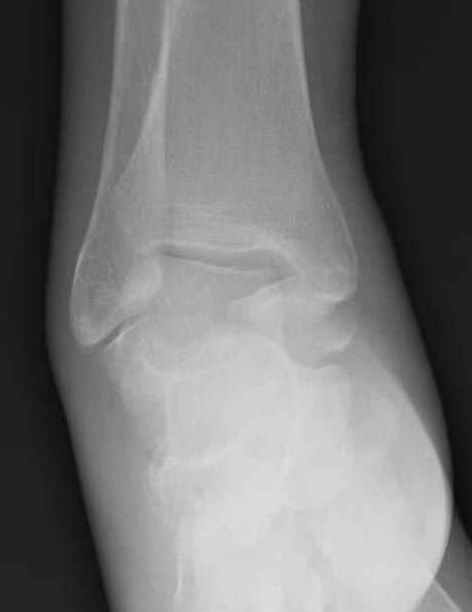

Повреждение таранной кости

из

Какие рекомендации? Djoldas Kuldjanov, MD Department of Orthopedic Surgery St. Louis University Medical Center